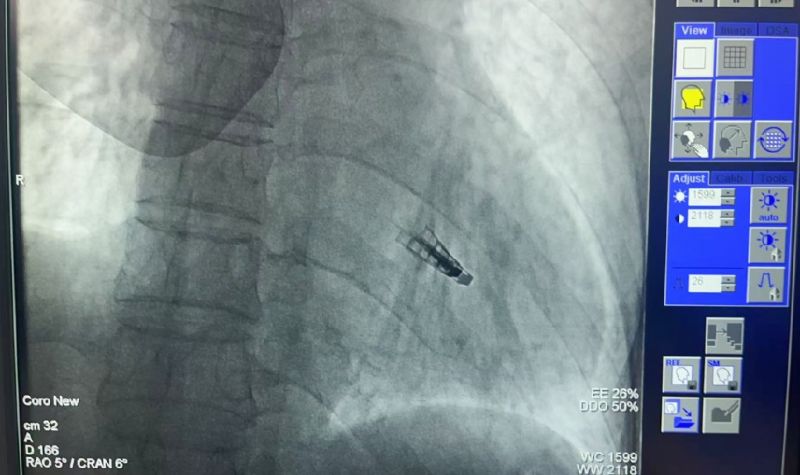

2025年5月9日,延安大學咸陽醫院常務副院長兼心血管病院院長吳棟梁介入團隊成功為一名73歲“二尖瓣大量返流”患者實施咸陽市首例《經導管二尖瓣緣對緣修復術(TEER)》。

創傷極小:不開胸的“心臟修補術”。僅通過股靜脈穿刺,經導管送入夾合器精準修復二尖瓣,避免傳統開胸、體外循環等高風險操作。

高效精準:手術耗時僅1-2小時,術后患者即刻返流顯著減少,血流動力學明顯改善。

術前吳棟梁院長、劉雄濤院長、張樹遠責任總醫師再次深入的評估患者整體病情及手術指征,于2025年5月9日下午成功為患者實施了TEER技術,解除了其病痛,術后第一天患者即表示“呼吸順暢了,整個人都輕松了”。